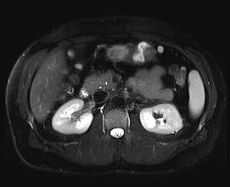

Snímek z magnetické rezonance

Snímek břicha (ledvin) pořízený 3 Tesla magnetickou rezonancí